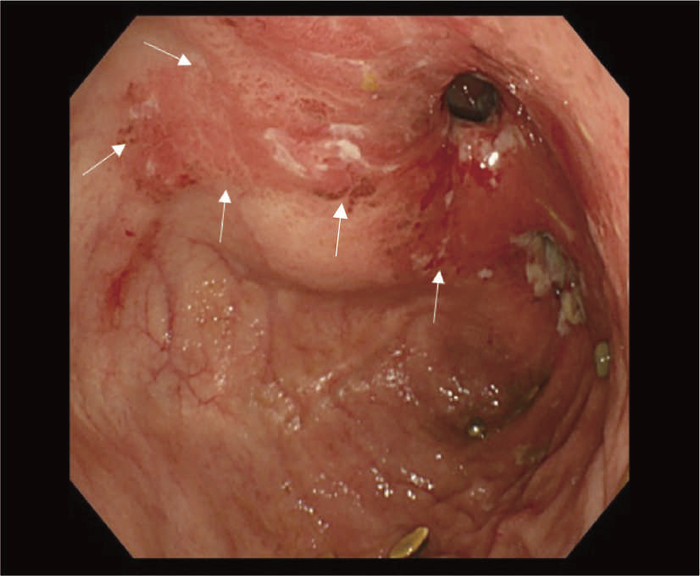

通常の散発性進行大腸癌の多くは潰瘍限局型(2型)であるが,UC関連進行大腸癌は潰瘍浸潤型(3型),びまん浸潤型(4型)や分類不能型(5型)が多いとされる(図7)。初期病変であるdysplasiaの肉眼形態に関しては,混合型を含む約70%の症例が何らかの隆起成分を有することが報告されている1,2)。ただ同じ隆起といっても,UC関連大腸腫瘍の多くは境界不明瞭な丈の低い顆粒状・結節状・不整扁平隆起を呈する一方で,散発性腫瘍は有茎性もしくは亜有茎性病変,境界や立ち上がりが明瞭な病変であることが多く,詳細な肉眼形態の観察は両者の鑑別に重要である。二番目に多い肉眼形態は平坦型であり,全体の約30%を占める1,2)。散発性大腸腫瘍の平坦型は極めて頻度が低いことから,平坦型成分の存在もdysplasiaの特徴といえる(図8)。

- 内腔狭窄を伴った5型の腫瘍(矢印)を認める。

- 組織学的には,粘液癌あるいは低分化腺癌が壁内に浸潤している像を認める。